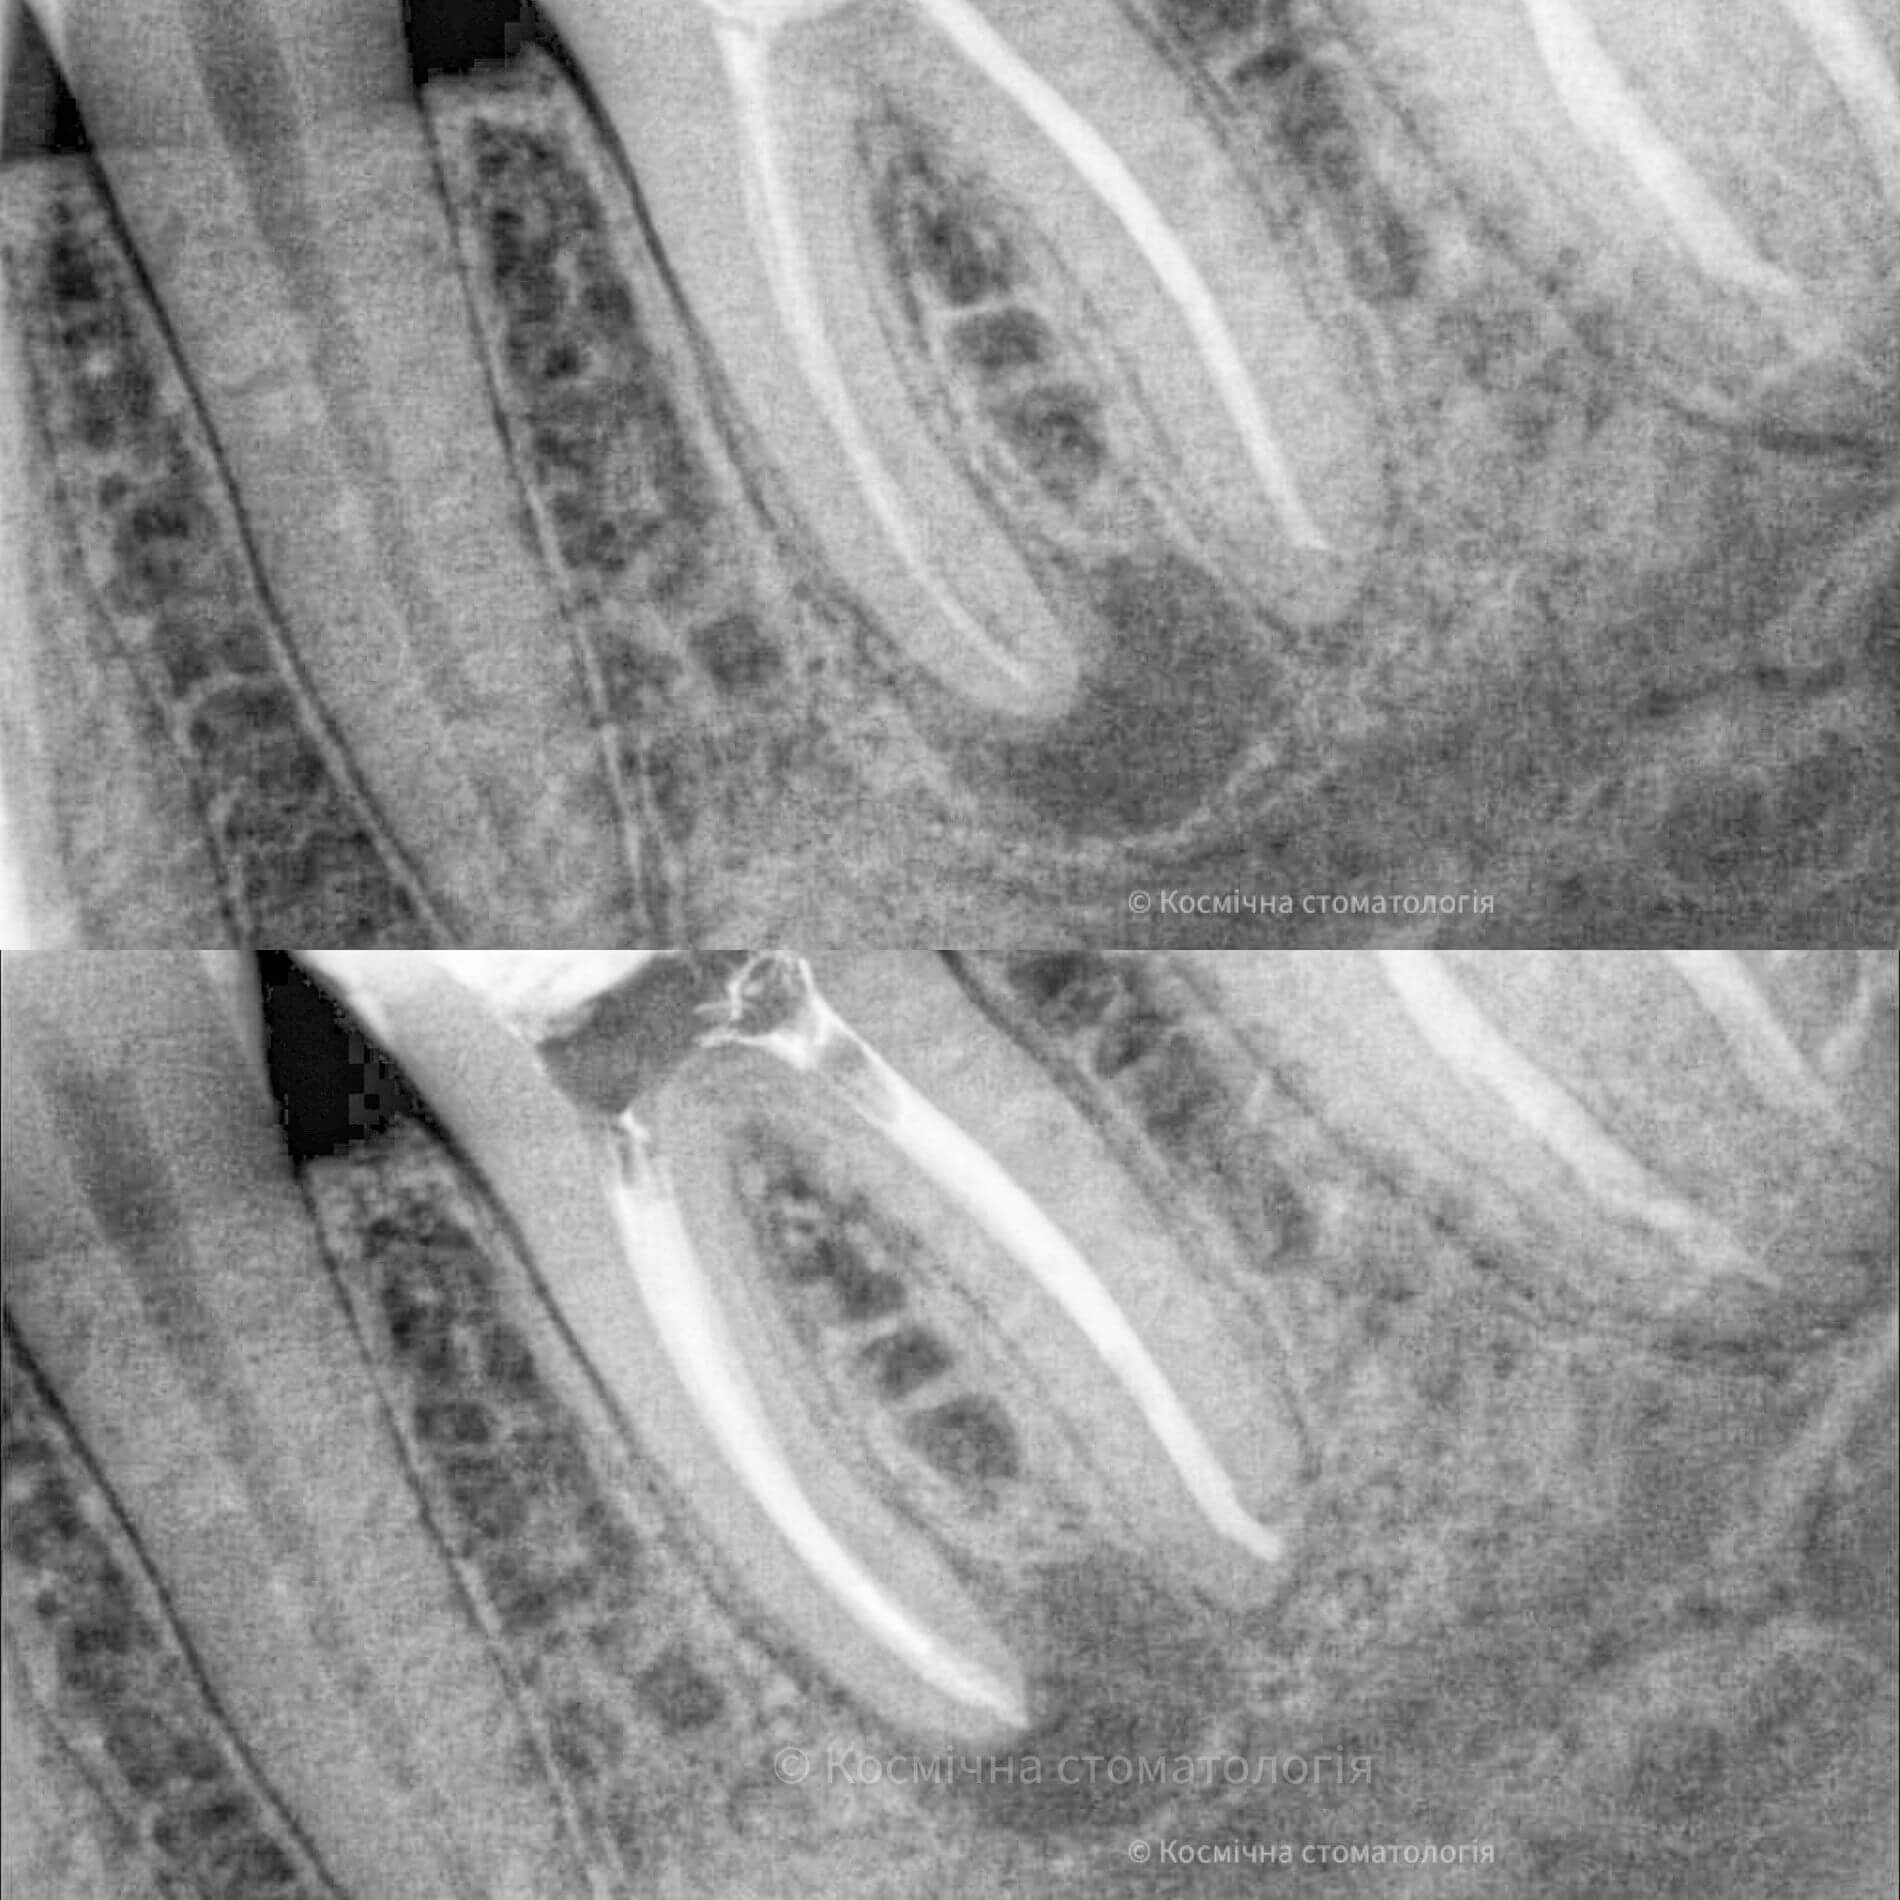

- 3D пломбирование корневых каналов горячей гуттаперчей. Высокоэффективная техника, позволяющая заполнить все ответвления корневых каналов настолько плотно, чтобы достичь абсолютной герметизации. А значит, ни одна инфекция не сможет повторно поразить корневые каналы твоего зуба.

Чтобы провести процедуру лечения и пломбирования каналов, мы в космической стоматологии Драганчука используем оптическое увеличение с помощью микроскопа Carl Zeisse.

Он позволяет вывести изображение на большой экран и масштабировать его, чтобы наша космическая команда могла осуществить все необходимые манипуляции особенно скрупулезно. Благодаря такому оптическому контролю каждого этапа лечения, мы можем оценить его эффективность и предотвратить возникновение осложнений.